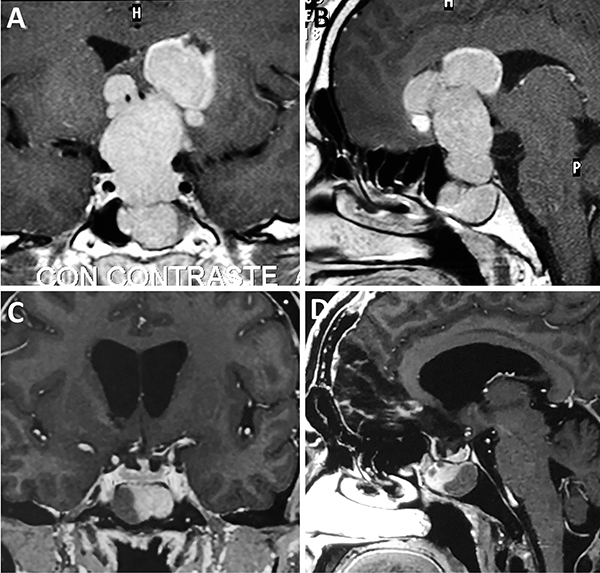

Una clasificación clásica de los adenomas es según su tamaño. Se los clasifica en microadenoma <10 mm (fig. 2), macroadenoma >10 mm (fig. 3), y adenoma gigante > 30 mm (fig. 4). Esta clasificación es importante ya que los índices de remisión están ligados al tamaño del adenoma y también su recidiva.12

Figura 4: Adenoma gigante. A-B: RM preoperatoria; C-D: RM postoperatoria.